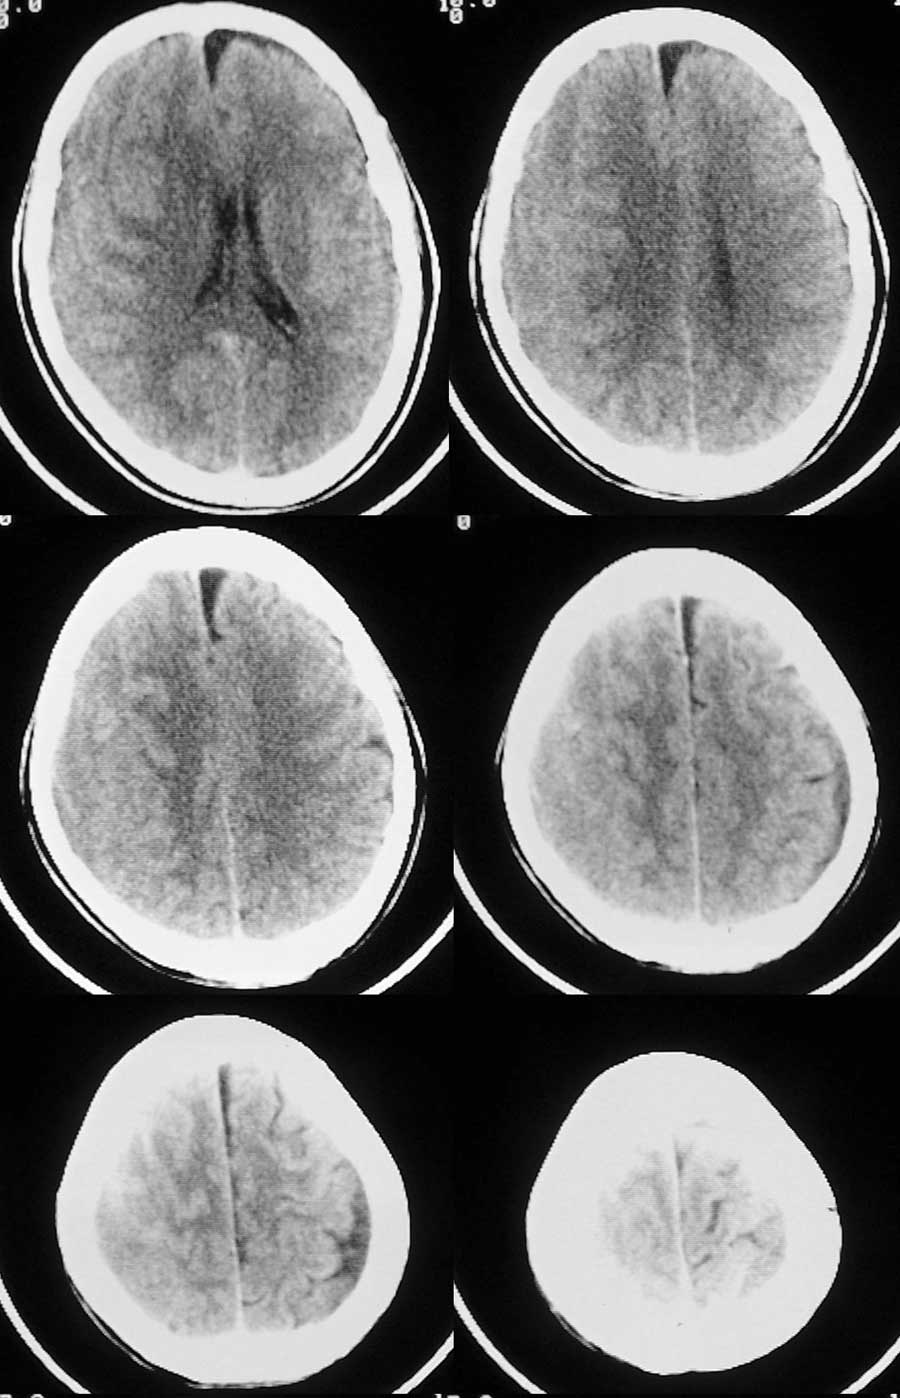

m/63岁,以左侧肢体麻木一周就诊;

右侧外侧裂、右侧脑沟均较窄,右侧灰白质均向左移位,中线结构亦左移。右侧颅板下见与皮层等或略低密度的条形影。

考虑:右侧亚急性硬膜下血肿。

右侧脑沟裂消失,皮髓质交界点内移,右侧脑室受压,慢性硬膜下血肿

1右额颞顶部慢性硬膜下血肿,2左硬膜下积液

右侧额';,颞,顶颅骨内板下可见弧低密度影,脑灰质移位,右侧外侧裂池及侧脑室,大脑半球脑沟变窄,应该是个慢性硬膜下血肿

左额叶慢性硬膜下积液

1、右侧额颞部亚急性硬膜下血肿 2、左侧额部硬膜下积叶

右侧额顶亚急性硬膜下血肿,等密度

有些硬膜下出血特别是老人多表现为等或略低密度,有时不易辨别,需用窄窗技术观察,大家平时工作中要提高警惕!

诊断:右侧亚急性慢性硬膜下血肿

补充:左侧额叶前边低密度考虑是硬膜下积液,对应脑组织有受压变圆钝,脑回消失;左侧顶叶低密度考虑是局限性脑萎缩 ,局部脑回正常,脑组织无受压迹象。

脑沟裂消失,皮髓交界区内移,中线结构左移考虑右额颞顶部慢性硬膜下血肿